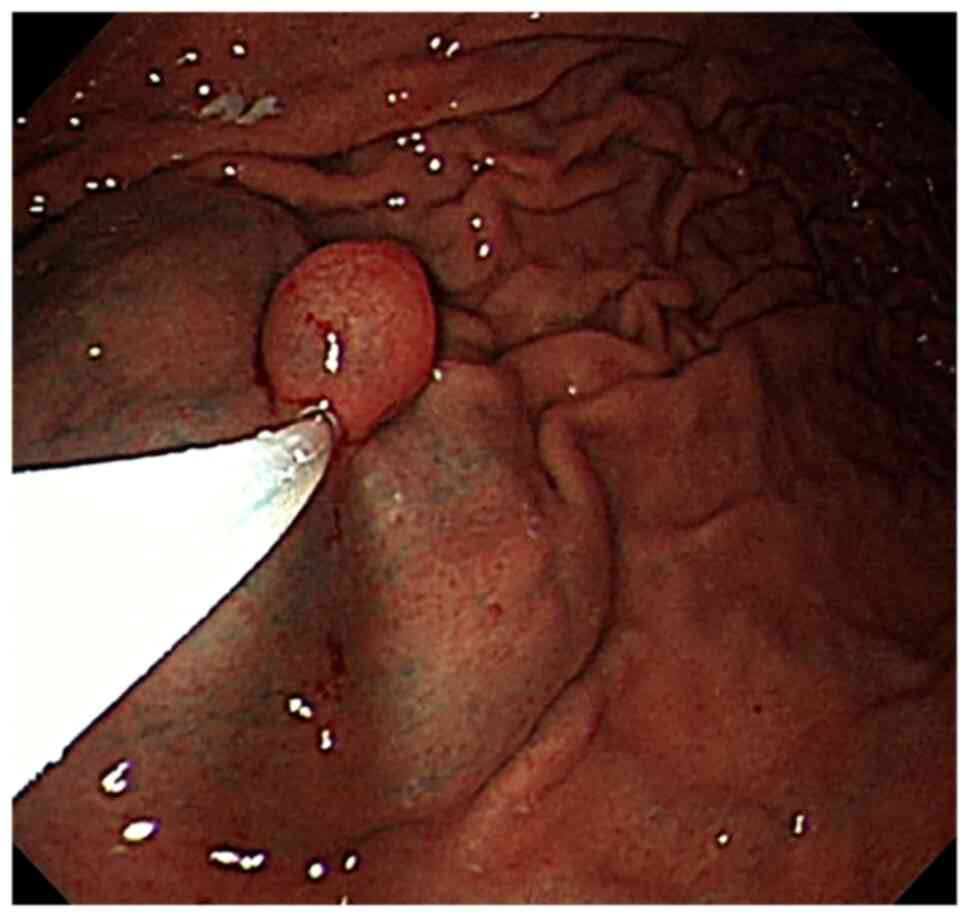

Gastric inverted hyperplastic polyp: A case report

Inverted hyperplastic polyp (IHP) is a rare disease characterized by the downward growth of proliferative mucosal components into the submucosal layer. It is often misdiagnosed as other submucosal tumors and accurate diagnosis requires pathological examination. Most patients with IHP have no clinical symptoms and some have non‑specific symptoms, such as abdominal distension, abdominal pain and even anemia. IHP is treated via endoscopic mucosal resection or endoscopic sub‑mucosal section. The present study reported a case of IHP and discussed its clinical manifestations, clinicopathological diagnosis, differential diagnosis and treatment to improve our understanding of the disease.

Figure 1

Figure 2

Figure 3

Figure 4

Figure 5

Figure 6

Figure 7